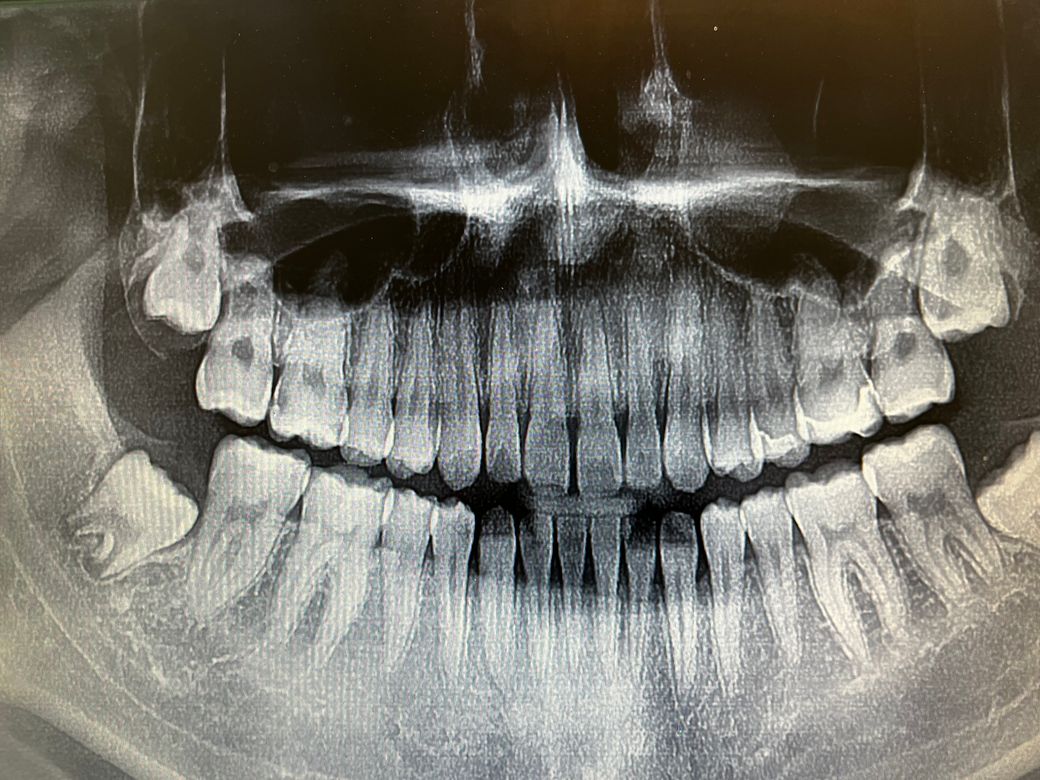

지난달에 인레이를 ㄷ자 모양으로 했습니다 근데 그부분이 어금니라 아랫니랑 안맞아요 오늘 크라운 최종치료를 하고나니 크라운쪽만 닿는게 확실리 느껴지더라구요 사진은 인레이쪽 입니다 사진에서 오른쪽ㄷ자요 크라운을 안했을땐 별로 못느꼈는데 지금은 차이가 너무 나요 어떻게 해야하죠? 크라운한 병원을 가서 크라운을 낮춰야할까요 인레이 한 병원을 가서 교합을 받아야할까요?

크라운하기 전에는 괜찮으셨다면 크라운을 하는 병원에서 우선 말씀을 드리고 크라운이 없을때도 인레이쪽이 안닿는지 먼저 확인하시는게 좋겠습니다. 크라운 때문이라면 크라운을 조절하면 되겠지만 크라운이 없을때도 안닿는거라면 인레이를 재제작 하셔야할 수 있으니 이런 경우 인레이 한 치과로 가셔야합니다.

크라운 한 후 크라운 한쪽만 닿으면 크라운이 높은 것입니다 인레이치료후에는 괜찮았다면 말이죠

일단 크라운에 대해서 교합조정 시행하고 그 이후에도 인레이쪽이 불편하고 교합이 안맞는다고 느껴지면 그때 인레이 조정합니다